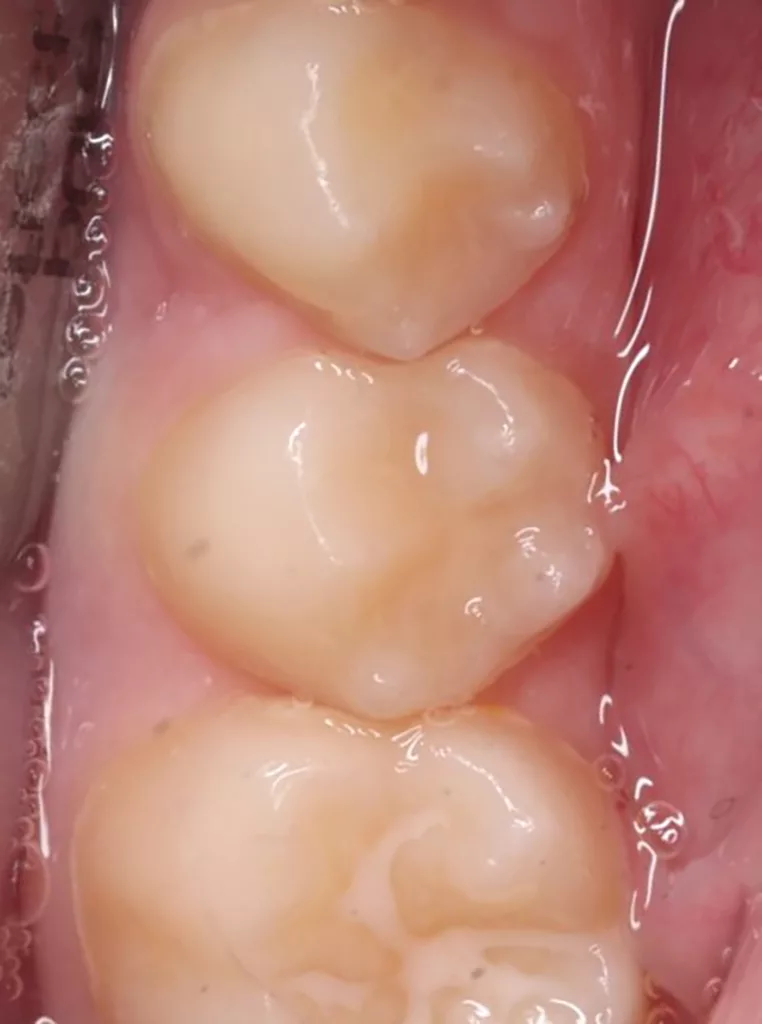

Unter Lokalanästhesie mit dem STA-System (Milestone Scientific, USA) und Septanest 1/200 000 (Septodont, Frankreich) wurde die überstehende Gingiva mit dem Khors Koagulator (Эctatex, Ukraine) koaguliert und der Bereich unter Kofferdam kontaminationsfrei dargestellt (Klammer U67, KSK Dentech, Japan). Die schmalen Fissuren wurden mit dem Fissurenbohrer CD-53F (Mani, Japan) erweitert, um anschließend mittels RONDOflex plus 360 (KaVo Dental, Deutschland) und Pulver 27 µm vollständig gereinigt werden zu können. Es konnte weder durch visuelle Inspektion noch Sondierung mit 0.08 H-file (Mani, Japan) ein Defekt des Zahnschmelzes festgestellt werden. Unter Berücksichtigung der Integrität des Zahnschmelzes, der Symptomlosigkeit, des Behandlungszeitpunktes, Alters des Kindes und Wachstums der Zahnwurzeln fiel gemeinsam mit den Eltern die Wahl auf eine konservative Therapie. Es wurde eine Fissurenversiegelung mit Clinpro Sealant (3M, USA) unter Anwendung eines adhäsiven Behandlungsprotokolls mit Optibond FL (Kerr, USA) durchgeführt. Dieser klinische Fall ist dahingehend einzigartig, da alle anderen ersten und zweiten Molaren des Kindes ebenso von einer PEIR betroffen waren (Grad 1 bis 2 der Läsion nach Seow) (Abb. 3 und 12). Normallerweise ist nur ein Zahn bei einer Patientin oder einem Patienten betroffen. Die Zahnkronen der anderen betroffenen Zähne erwiesen sich bei der klinischen Untersuchung als intakt; die radioluzenten Läsionen innerhalb des koronalen Dentingewebes waren wesentlich kleiner als die von Zahn 36. Daher wurde auch bei diesen Molaren das gleiche Behandlungsprotokoll angewendet und nur eine Fissurenversiegelung durchgeführt.

Im Rahmen der jährlichen Kontrolluntersuchung wurde bei einem achtjährigen Mädchen auf der routinemäßig angefertigten Röntgenaufnahme eine mittelgroße PEIR des Zahnes 46 (Grad 2 der Läsion nach Seow) entdeckt (Abb. 43). Die Patientin war komplett beschwerdefrei und der Zahnschmelz des betroffenen Zahnes sah intakt aus (Abb. 44 und 45). Weil auch hier der PEIR-Defekt gräulich durchschimmerte (Abb. 44 und 45) und der Zahn bereits seit einem Jahr durchgebrochen war, entschieden wir uns in diesem Fall, den Defekt klassisch mit Komposit zu restaurieren. Unter Lokalanästhesie mit Septanest 1/100 000 (Septodont, Frankreich) wurde zunächst Kofferdam mithilfe der Klammer U67 (KSK Dentech, Japan) gelegt (Abb. 45). Weder visuell noch mittels Sondierung konnte eine Verbindung zur Läsion festgestellt werden. Deswegen wurde an der Stelle, an welcher der PEIR-Defekt gräulich schimmerte, intakter Zahnschmelz der lingualen Querfissur entfernt (Abb. 46). Innerhalb der Läsion wurde nekrotisches intrakoronales Weichgewebe vorgefunden (Abb. 47), das problemlos mittels RONDOflex plus 360 (KaVo Dental, Deutschland) mit dem 27-µm-Pulver vollständig entfernt werden konnte. Der Boden des Defektes zeigte eine glatte, runde Form sowie helles, hartes und intaktes Dentin. Eine Präparation war nicht erforderlich, es wurde lediglich die Zahnschmelzkante geglättet (Abb. 48). Für die Restauration kamen erneut das Adhäsiv Optibond FL (Kerr, USA) und das Komposit Estelite ASTERIA OCE, A2B und Universal Flow AO2 (Tokuyama, Japan) zur Anwendung (Abb. 49). 6 Monate nach der Behandlung zeigte sich das Ergebnis sowohl aus klinischer als auch radiologischer Sicht stabil wie die Abbildungen 50 und 51 zeigen.